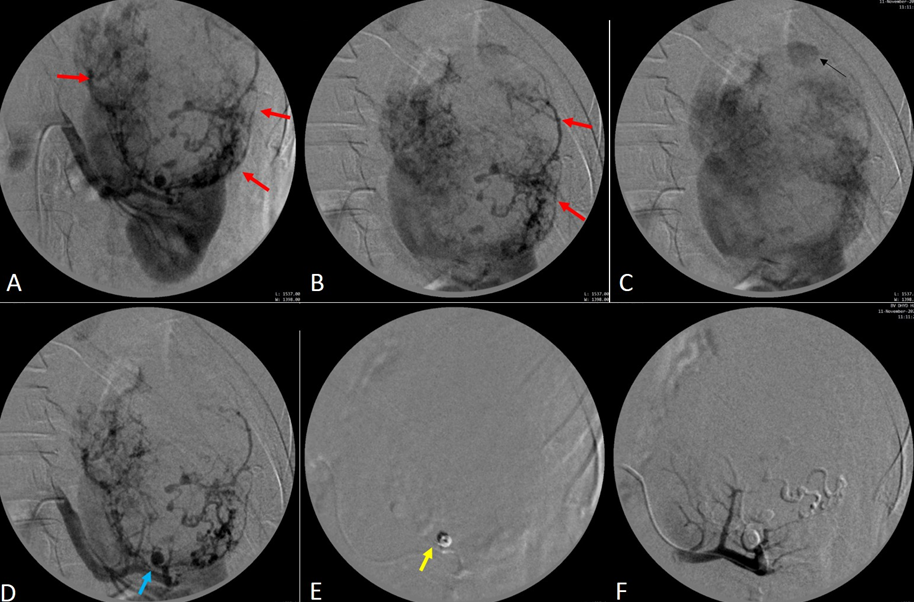

Bệnh nhân được giải thích đầy đủ về tình trạng hiện tại, phương pháp điều trị, ưu nhược điểm của phương pháp và các nguy cơ có thể xảy ra. Thủ thuật được tiến hành vào ngày 11/11/2020 (Hình 2).

- Chụp động mạch thận trái thấy khối u lớn ở thùy trên, bên trong có nhiều mạch máu dị dạng giãn ngoằn ngoèo và ổ phình mạch dạng túi. Chọn lọc nhánh mạch nuôi và nút mạch đầu xa bằng hạt vi cầu Embozene 250µm và PVA contour 355-550µm. Nút túi phình mạch bằng coil Interlock 4x8mm. Chụp kiểm tra thấy tắc hoàn toàn nhánh mạch nuôi.

- Tưới máu cho nhu mô thận còn lại bảo tồn.

Hình 2. Hình A và B: Chụp mạch số hóa xóa nền (DSA) động mạch thận trái: Khối u mạch cơ mỡ lớn ở thận trái (mũi tên đỏ) với hình ảnh mạch máu tăng sinh và phình mạch ở cực dưới u (mũi tên xanh). Hình C: đặt coil (mũi tên vàng) vào phình mạch cực dưới u. Hình D: Chụp DSA sau can thiệp: Khối u và phình mạch đã bị nút tắc hoàn toàn không còn dòng chảy.